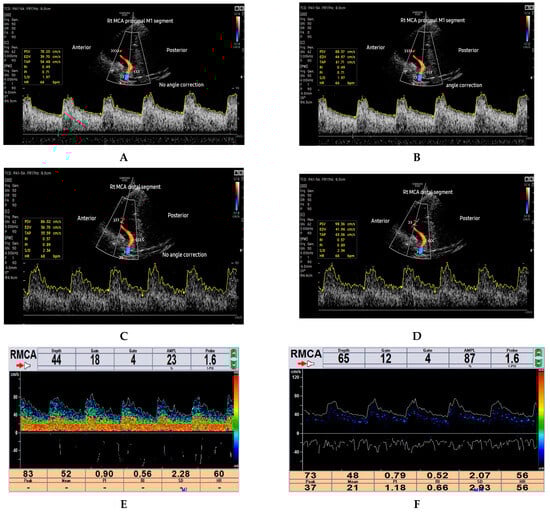

The ultrasound machine settings for the current study involved optimising the main parameters of B-mode ultrasound, such as power output, frequency, overall gain, time gain compensation (TGC), focusing, and depth. The optimisation was primarily achieved through the selection of a user-defined optimised preset under the TCD application available on the RS85 Samsung ultrasound machine (power output = 90%, frequency = general preset, dynamic range = 50, frame average = 8, scan area = 100%, focus = 1, and gain = 50). Minor adjustments to suit individual subjects were performed during the actual scanning. The depth would be increased to visualise the contra-lateral temporal skull bone and later adjusted to ensure that the ROI corresponding to ipsilateral proximal and distal MCA segments occupies at least 2/3 of the field of view (FOV) during velocity measurements, as shown in Figure 1A–D. A single focal zone was utilised and set at the level of the ROI to enhance lateral resolution. Additionally, color and spectral Doppler settings were optimised throughout the study. The color gain was optimised by first increasing the color gain until noise signals appeared, depicted as a vessel-bleed artifact outside the MCA blood vessel, then gradually decreased until the noise disappeared. The velocity scale or pulse repetitive frequency (PRF) was optimised by decreasing it until the aliasing artifact appeared and then increased to an optimum point until the aliasing artifacts disappeared. Furthermore, the sample volume was set at 4 mm for both the TCCD and TCD techniques. The typical B-mode, color, and spectral machine settings parameters used in this study are depicted in Supplementary Table S1.

In the B-mode axial scan plane, the mesencephalic brain stem structures were identified as hypoechoic, butterfly-shaped structures surrounded by a hyperechoic star-shaped basal cistern. Color Doppler imaging mode was then turned on to identify the ipsilateral MCA at the circle of Willis. Once the ipsilateral MCA was ascertained on color Doppler mode, a set of three consecutive measurements of the haemodynamic parameters (PSV and MFV) were performed at the two ROIs for the TCCD test methods (1) ncTCCD and (2) cTCCD using an automated spectral Doppler waveform analysis. The median of the three measurements was considered for data analysis. In ncTCCD, blood flow velocities were measured without applying angle correction. In cTCCD, the cursor for angle correction was applied and aligned parallel to the color Doppler blood flow direction before measuring the blood flow velocities, according to Polak et al. [28]. The same procedure was repeated by scanning the other side of the head. The MFV acquired in the TCCD techniques was represented by the time-averaged peak velocity (TAP). After completing the TCCD examinations, participants then proceeded to undertake the TCD examinations. During the TCD examination, the subjects were insonated via the same TTW location used in the TCCD examination using a 1.6 MHz hand-held probe. The uni-channel mode on the Delica EMS-9PB TCD machine was used, with the following typical parameters (probe frequency = 1.6 MHz, power output = 23.3, and gain—(8–18)). The sample volume depths were set at the two ROIs similar to those interrogated at TCCD, whereas a sample volume gate of 4 mm was similarly maintained across the techniques. An open TTW was defined as the ability to visualise the midbrain structures on the grayscale ultrasound image and the ipsilateral MCA. The ROIs and the Doppler signal acquisition techniques are shown in Figure 1A–F.

Figure 1. Images of a 40-year-old healthy subject showing the ROIs and the Doppler signal acquisition techniques: (A) ncTCCD measurement of PSV and TAP of proximal MCA (triple arrowheads), (B) cTCCD measurement of PSV and TAP of proximal MCA (triple arrowheads), (C) ncTCCD measurement of PSV and TAP of distal MCA (triple arrowheads), and (D) cTCCD measurement of PSV and TAP of distal MCA (double arrowheads). (E) TCD waveform showing measurement of PSV and MFV at a distal depth of MCA, (F) TCD waveform showing measurement of PSV and MFV at a proximal depth of MCA. The long vessel color-coded in red is the right MCA, whereas the ipsilateral anterior cerebral artery segment is color-coded in blue.